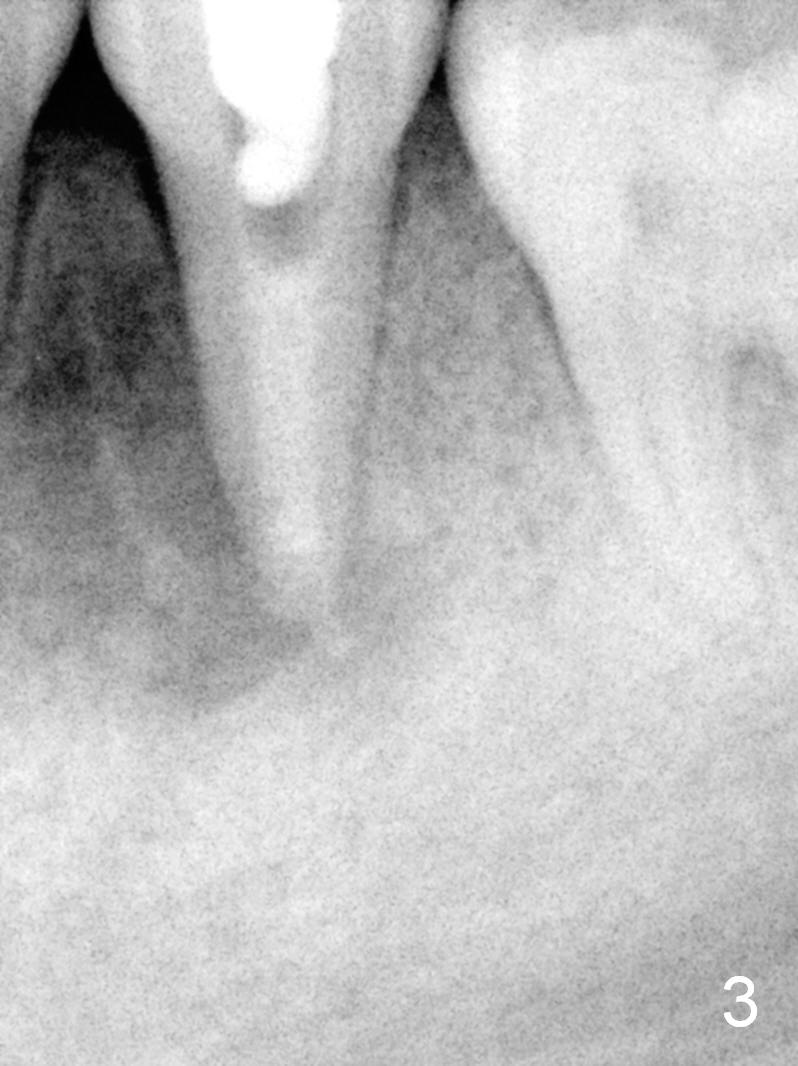

A 13-year-old girl has a buccal apical fistula at the tooth #20 with large periradicular radiolucency (Fig.1 *). After canal debridement, calcium hydroxide paste is placed in the canal (Fig.2 *). One month later, the fistula does not disappear with light percussion. New paste is placed (Fig.3). Two months later, the fistula disappears without percussion. The existing paste (Fig.4) is changed (Fig.5 (yellow: radiolucency; red: Inferior Alveolar Canal)). Another 2 months later, the fistula does not recur; as before, the paste density decreases, so does periradicular radiolucency (Fig.6). Root canal is packed (Fig.7). Six months postop, periradicular radiolucency continues to decrease, while the lamina dura at the apex is discontinuous (Fig.8 between arrowheads). Seven years postop, the lamina dura at the apex is seemingly intact (Fig.9). The patient remains asymptomatic at #20. In fact there is an acute infection at #29.